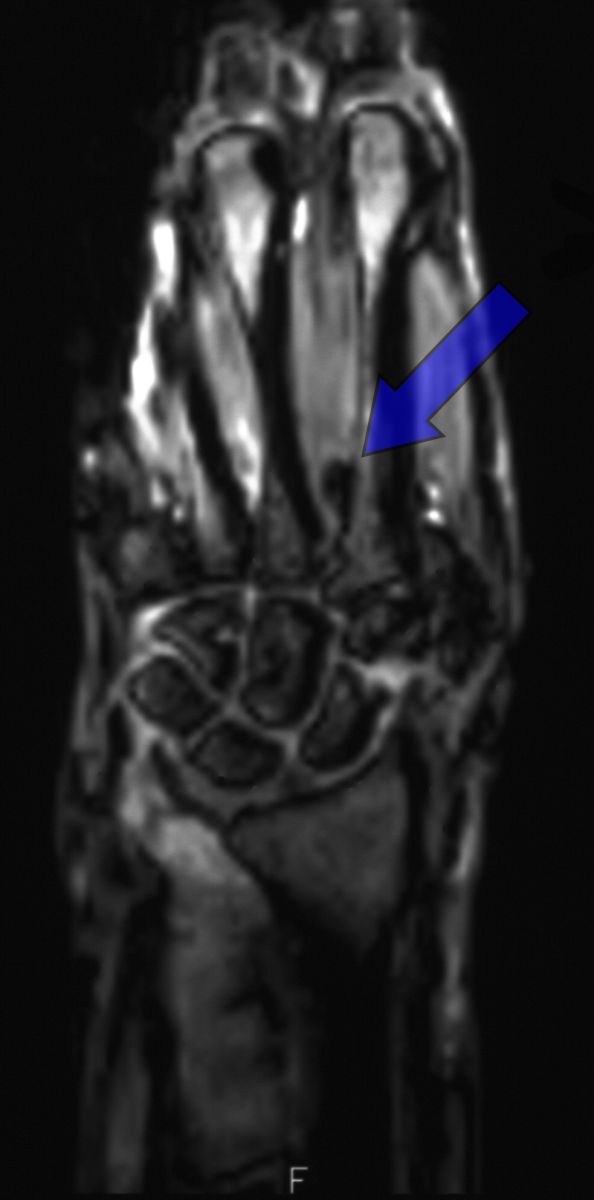

| 18 months postop, MRI for

an unrelated diagnosis demonstrates the tendon loop path in the

intermetacarpal space. |